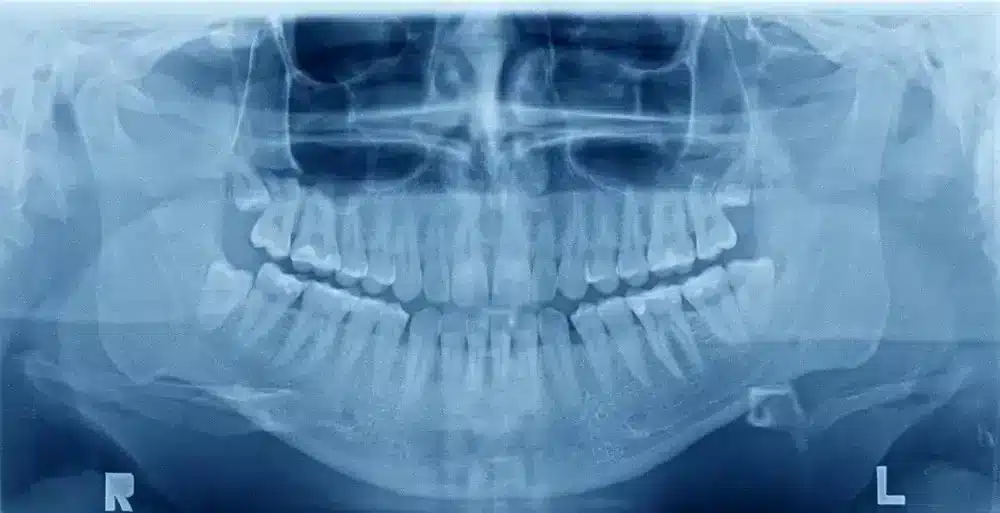

Panoramic X-Rays: A Comprehensive View of Oral Health

A key advancement within digital X-ray is the panoramic X-ray, which captures a broad view of the entire mouth, including the teeth, jawbone, and surrounding structures. This type of imaging provides valuable information that can guide treatments for various dental concerns, such as:

- Impacted teeth (e.g., wisdom teeth)

- Jaw disorders (e.g., TMJ)

- Oral cancers

- Bone abnormalities

Panoramic X-ray are particularly helpful for planning complex procedures, such as dental implants or orthodontic treatment, as they provide a complete view of the patient’s oral anatomy.